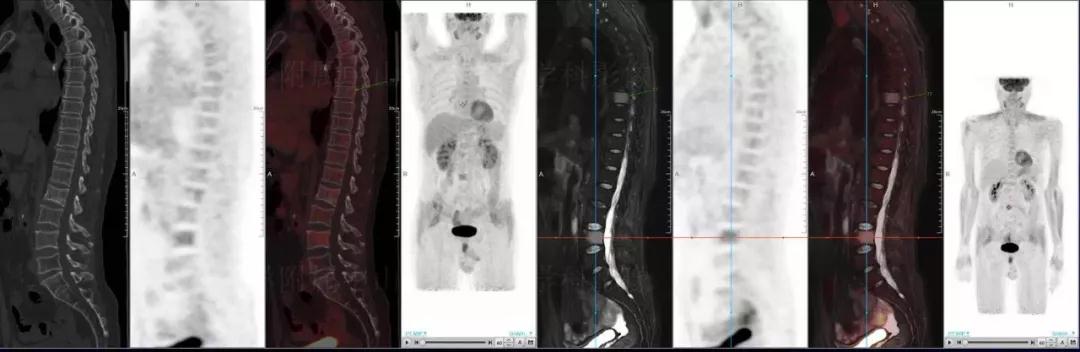

中山醫(yī)院核醫(yī)學(xué)科基于聯(lián)影“時(shí)空一體”超清TOF PET/MR的融合顯像優(yōu)勢,進(jìn)行了大量的臨床掃描,發(fā)現(xiàn)多例由MGUS向多發(fā)性骨髓瘤轉(zhuǎn)變,并從中總結(jié)出了一定的共同征象,未來可能實(shí)現(xiàn)多發(fā)性骨髓瘤的早期篩查。此外,PET/MR在多發(fā)性骨髓瘤的療效評(píng)估方面,也存在顯著優(yōu)勢。

(男性,53歲。確診多發(fā)性骨髓瘤10月。經(jīng)過7周期VCD方案化療后,現(xiàn)行療效評(píng)價(jià)。)